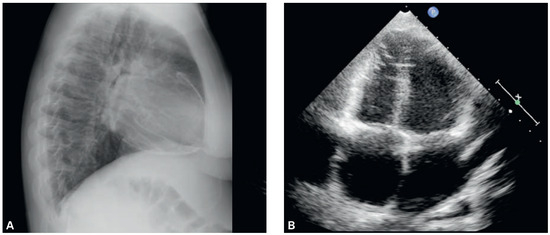

Heart Failure in a Young Lady from Tibet

by Magdalena Stepien, Sonja Bertschy, Xavier Mueller, Alexander Schipf and Florim Cuculi

This article reports a case of tuberculous constrictive pericarditis in a young migrant from Tibet. In developed countries this is a rare cause of heart failure; however, in the era of globalisation it should be considered as a possible differential diagnosis, especially in [...] Read more.

This article reports a case of tuberculous constrictive pericarditis in a young migrant from Tibet. In developed countries this is a rare cause of heart failure; however, in the era of globalisation it should be considered as a possible differential diagnosis, especially in patients coming from ende m ic areas. It also illustrates the importance of the chest X ray as an inexpensive and noninvasive method providing early diagnosis in affected patients. Full article

Figure 1